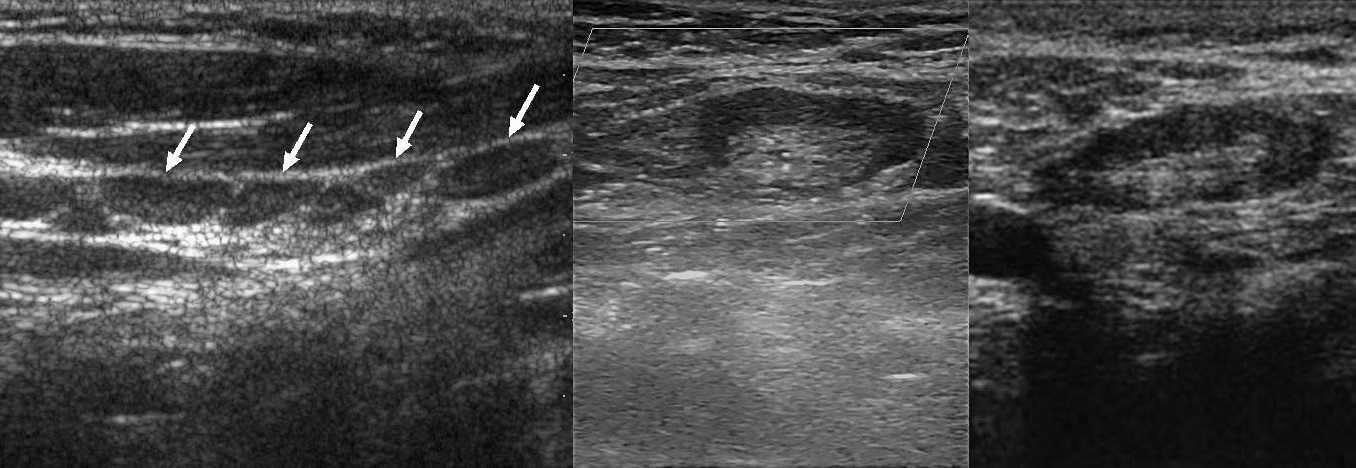

Рисунок. На УЗИ нормальные лимфоузлы в заднем треугольнике шеи у девочки 9-ти лет (1), лимфоузел яремной цепи у пожилой женщины (2), подмышечный лимфоузел (3). На участках ограниченных фасциями лимфоузлы более вытянуты в длину, чем которые располагаются в рыхлой клетчатке.

Поперечный срез мышцы или сосуда можно ошибочно принять за лимфоузел. В режиме ЦДК легко отличить лимфоузел от сосуда. Если датчик развернуть на 90°, то сосуды и мышцы представляют собой трубчатую структуру, а лимфоузел имеет овальную форму независимо от среза.

Рисунок. На УЗИ гипоэхогенные округлые образования похожие на лимфоузлы (1). Датчик развернули на 90°, слева видно гипоэхогенный овальный лимфоузел (красная стрелка), а в справа — продольный срез мышы (желтые стрелки).